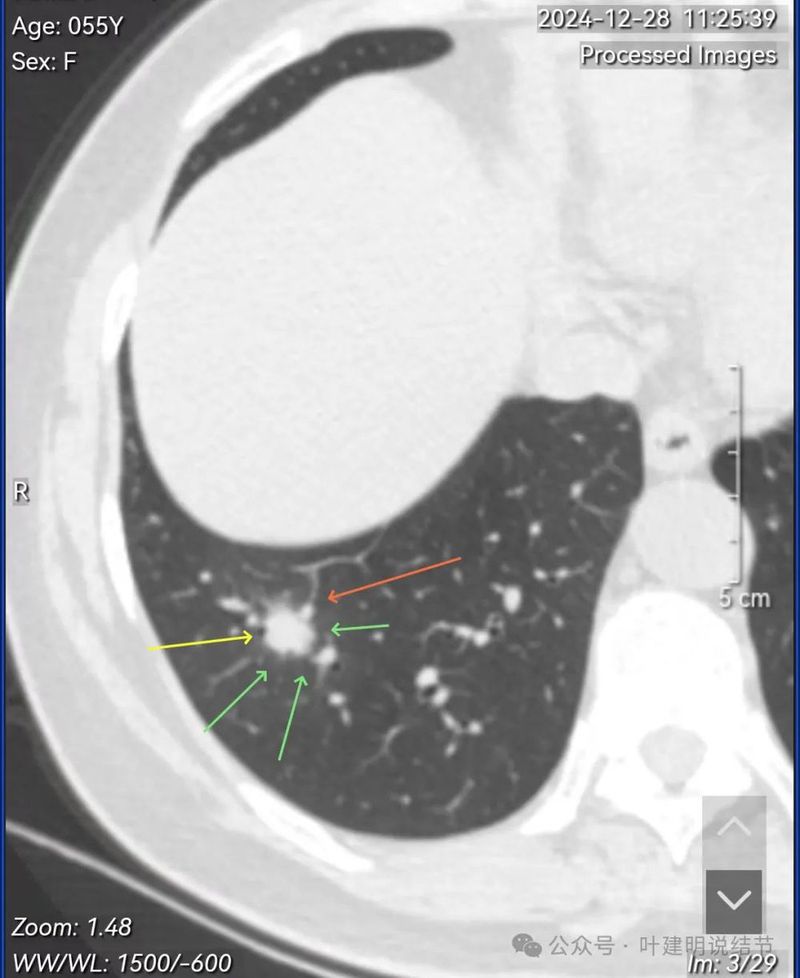

先看2024年12月28号初检查发现时的影像与报告:

右下病灶混合密度,整体轮廓较清,但瘤肺边界欠清晰。

实性成分占比高,边缘看上去有晕似的,边上有明显血管走行。也有细支气管可见。

实性部分或整体病灶缺乏收缩力,膨胀感也不明显。瘤肺边界欠清晰,感觉有一圈晕。

晕征上图更明显,进入的血管未见明显异常增粗,略显弯曲。

报告示右下叶外基底段结节,考虑肿瘤可能性大。